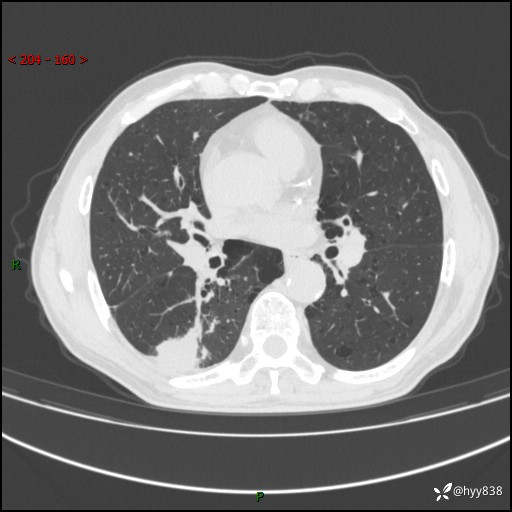

老年男性,发现右下肺结节3天。结节+卫星灶,似曾相识---结果公布~

简要病史:患者3天前于我院常规体检时行胸部CT提示“右下肺结节35mm*24mm”,自觉无发热、咳嗽、咳痰,无胸痛、咯血、气促加重,无声嘶、吞咽困难,无乏力、盗汗、体重减轻等不适。为求进一步诊治,入我院求诊,门诊以“右下肺结节待查”收入我科。患者3天前于我院常规体检时行胸部CT提示“右下肺结节35mm*24mm”,自觉无发热、咳嗽、咳痰,无胸痛、咯血、气促加重,无声嘶、吞咽困难,无乏力、盗汗、体重减轻等不适。为求进一步诊治,入我院求诊,门诊以“右下肺结节待查”收入我科。 起病以来,患者精神、食欲、睡眠可,体力稍差,大小便正常,体重无明显变化。

辅助检查:CT

胸部CT平扫